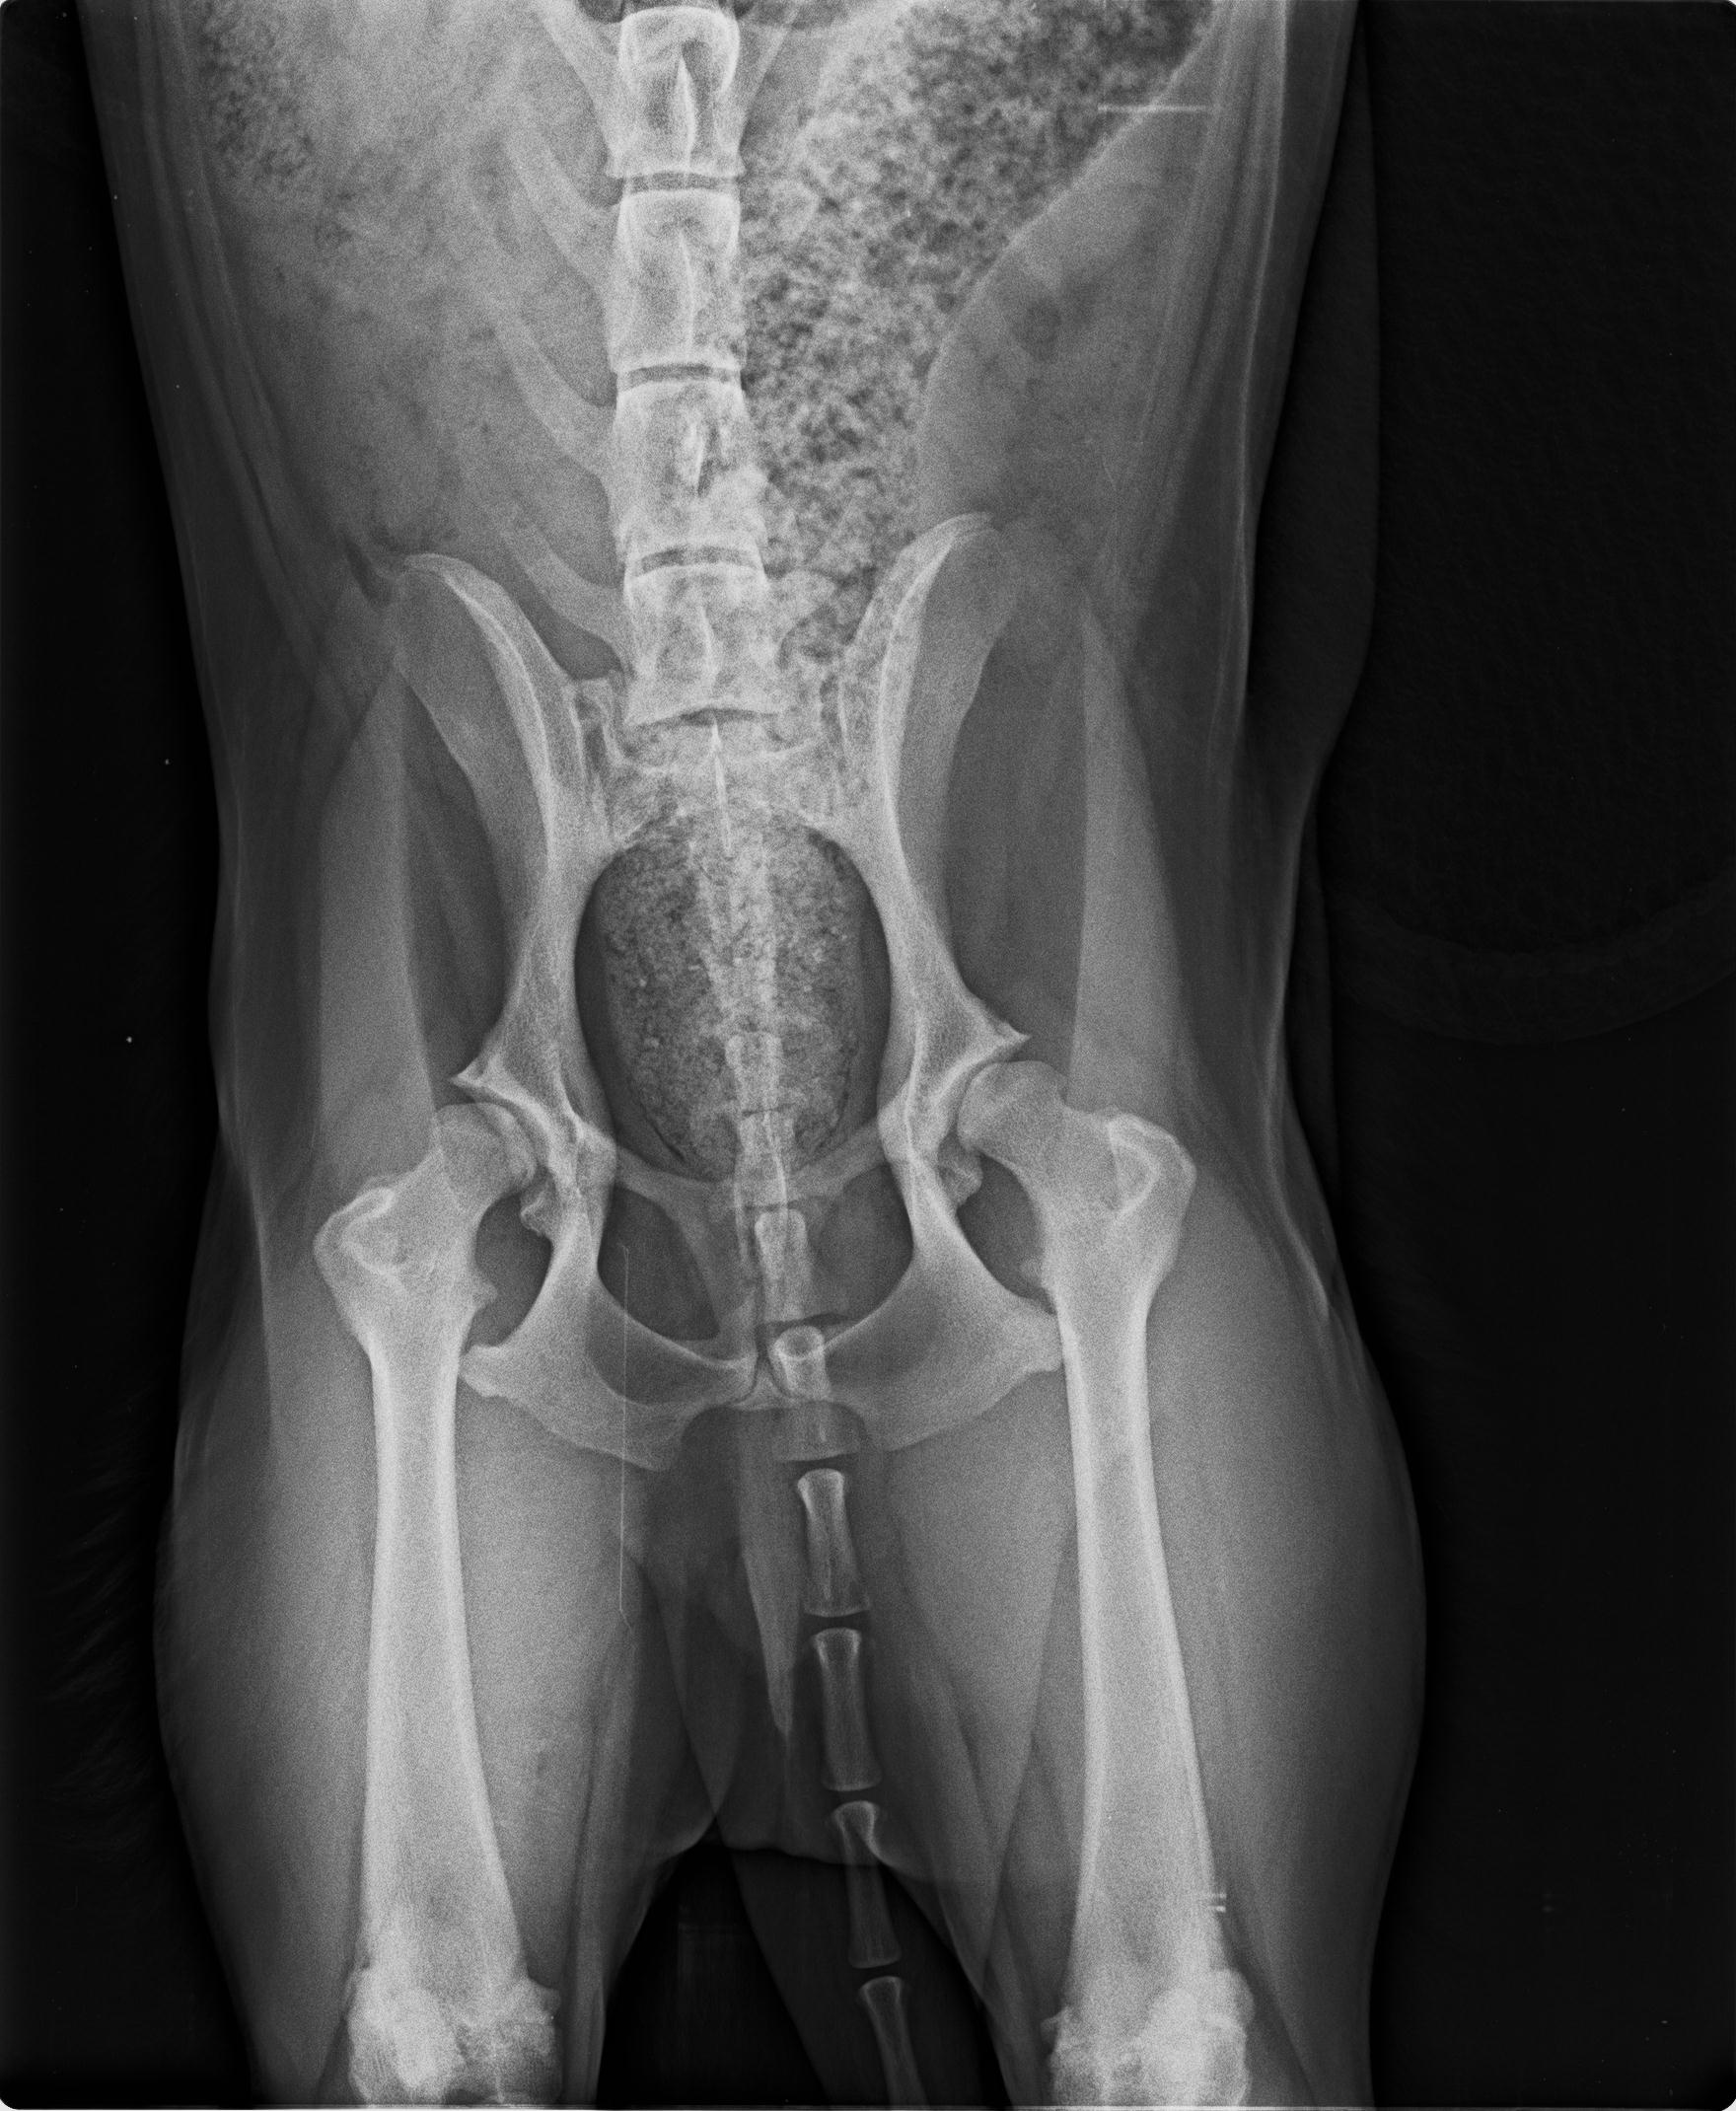

04.08.2025 neue Bilder, neues Video. Wir behandelten ihn mit Vitaminen und er schien sich gut zu entwickeln, er fing an, sich besser zu bewegen, obwohl wir mit der Zeit ein leichtes Hinken in seinem rechten Hinterbein bemerkten. Wir machten eine Röntgenaufnahme und der Tierarzt riet, den Oberschenkelkopf zu entfernen. Es dauerte viele Monate, bis er sich von der ersten Operation erholt hatte, so dass wir nicht wussten, ob wir auch das andere Bein operieren sollten. Aber dann begann Garfield, starke Schmerzen in seinem nicht operierten Bein zu haben. Wir gingen wieder zum Tierarzt und er wurde im Mai dieses Jahres an seinem zweiten Hinterbein operiert. Garfield ist ein Hund, der ein Zuhause mit einem großen Garten braucht, er ist kein Hund für Spaziergänge, da er sehr schnell müde wird. Vielleicht ist es eine Folge seiner Hinterbeinprobleme, als er ein Welpe war, deshalb sind seine Bedürfnisse anders als die anderer Hunde. Er wäre glücklich mit einem schönen, großen Garten, einer liebevollen und verständnisvollen Familie und viel Ruhe – mehr braucht Garfield nicht, um der glücklichste Hund der Welt zu sein.